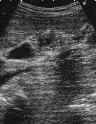

胆嚢腺筋腫症

右肋弓下縦走査